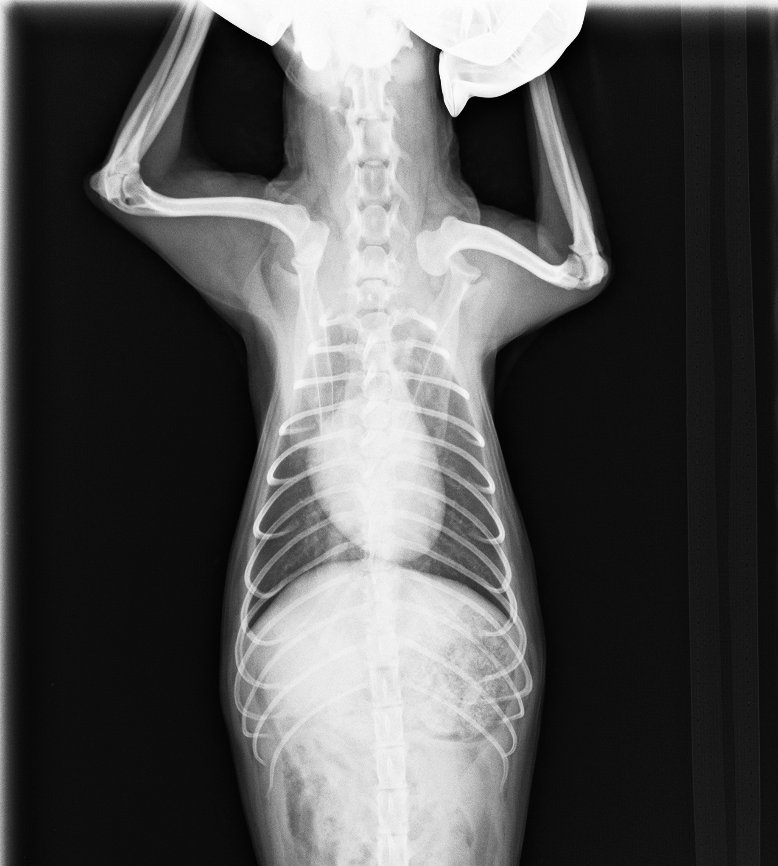

レントゲン検査より、右肩関節脱臼

診断と治療

右肩関節脱臼と診断し、スクリューを上腕骨に挿入し、肩関節を安定化させる

after